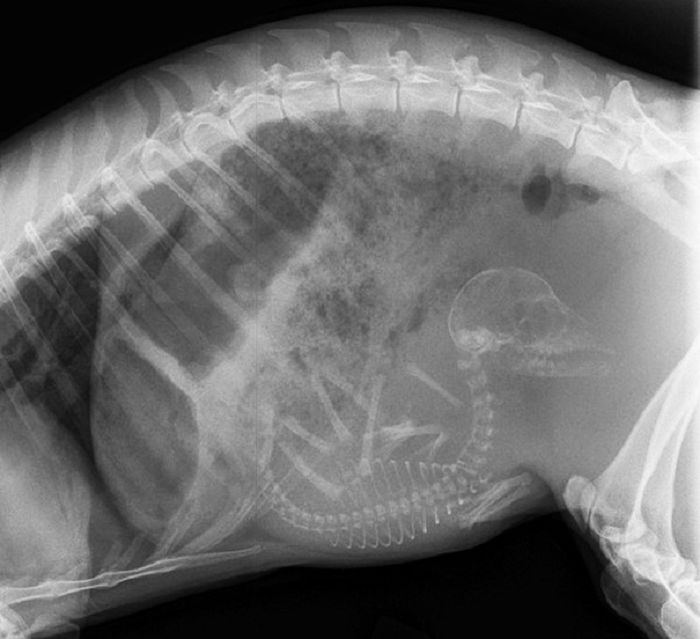

以下就是一些动物在怀孕时的X光片。

3. 狗